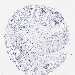

OVARIAN CANCER - Protein expressioni

A mouse-over function shows sample information and annotation data. Click on an image to view it in a full screen mode. Samples can be filtered based on level of antibody staining by selecting one or several of the following categories: high, medium, low and not detected. The assay and annotation is described here.

Note that samples used for immunohistochemistry by the Human Protein Atlas do not correspond to samples in the TCGA dataset.

Antibody stainingi

Antibody staining in the annotated cell types in the current human tissue is reported as not detected, low, medium, or high, based on conventional immunohistochemistry profiling in selected tissues. This score is based on the combination of the staining intensity and fraction of stained cells.

Each image is clickable and will lead to virtual microscopy that enables deeper exploration of all samples and also displays staining intensity scores, fraction scores and subcellular localization as well as patient and tissue information for each sample.

Antibody HPA036290

Staining

High

Medium

Low

Not detected

Intensity

Strong

Moderate

Weak

Negative

Quantity

>75%

75%-25%

<25%

None

Location

Nuclear

Cytoplasmic/membranous

Cytoplasmic/membranous,nuclear

Cystadenocarcinoma, serous, NOS

Carcinoma, endometroid

Cystadenocarcinoma, mucinous, NOS

Carcinoma, NOS